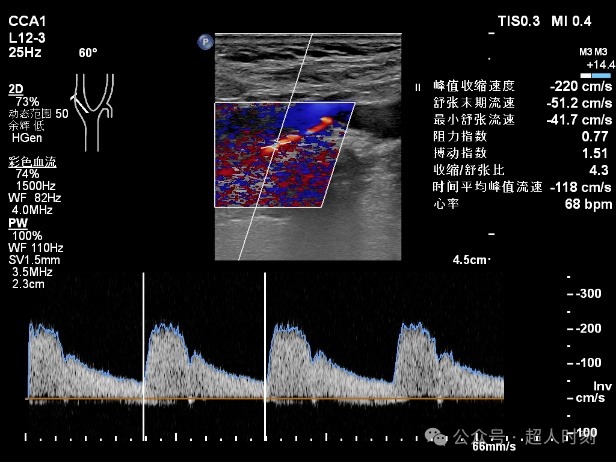

患者,男性,78岁,因“反复头痛头晕‚伴右眼黑朦1+年,肢体麻木偶感上肢无力6+月”入院。颈动脉彩超:右颈内动脉明显狭窄(狭窄率70%-99%),双侧颈总动脉多处狭窄(狭窄率<50%)。TCCD:颅内多支动脉狭窄(见图5)。

图5b 右颈内动脉颈段血流速度增快频谱图